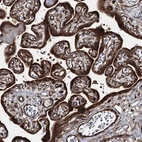

Immunohistochemical staining of human Prostate shows strong cytoplasmic positivity in smooth muscle and glandular cells.